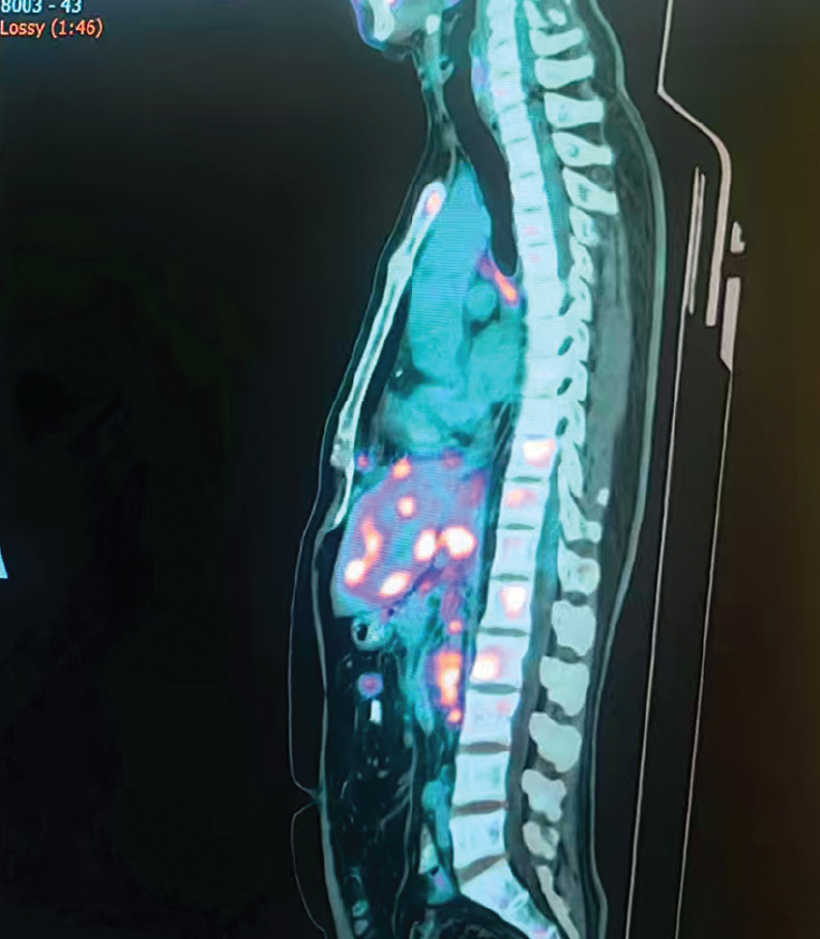

Treatment Plan:

GyroKnife + Electron Beam Therapy

– After 5 GyroKnife sessions, the lesion showed significant shrinkage and required repositioning

– Completed a total of 10 GyroKnife sessions, followed by 5 electron beam sessions

Within 2 months after discharge, lesions continued to shrink and entered the scarring/healing phase